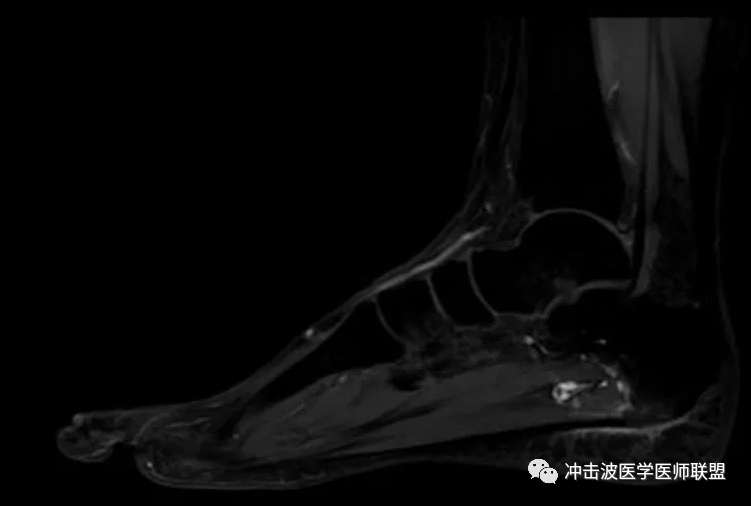

MRI檢查可以見到跟骨跖腱膜止點處的高信號,X線檢查還可見到跟骨下方有明顯的“骨刺”。